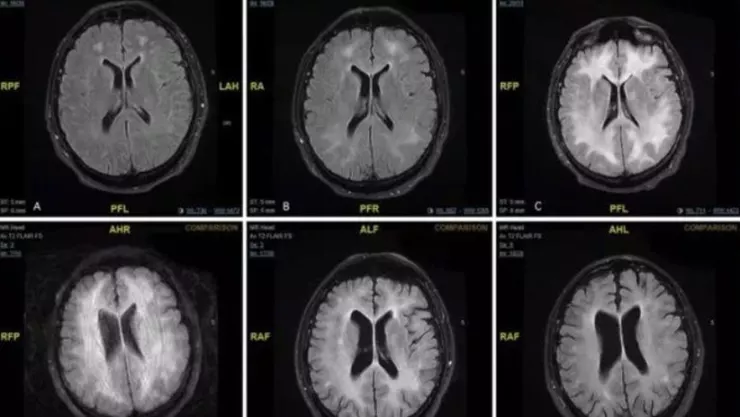

Un estudio determinó que tener un hipocampo grande no siempre se asocia con mejores habilidades de aprendizaje y memoria en los adultos mayores.

La investigación, sin embargo, descubrió que el volumen del hipocampo es sólo un marcador significativo de aprendizaje para las personas mayores con materia blanca límbica más intacta.

La materia blanca límbica es el circuito neuronal que conecta el hipocampo con el resto del cerebro. “Nuestros hallazgos resaltan la necesidad de medir no sólo el tamaño del hipocampo, sino qué tan bien está conectado con el resto del cerebro. Esta conexión se analiza cuando buscamos marcadores físicos de disminución de la memoria en adultos mayores”, dijo el responsable de la investigación, Andrew Bender, en un comunicado.

Para llegar a esta conclusión, los investigadores de la Universidad Estatal de Michigan, analizaron resultados de dos tipos diferentes de escáneres cerebrales por resonancia magnética: Uno evaluó el tamaño del hipocampo y otro el circuito de la materia blanca que conecta esta estructura con regiones del cerebro involucradas en el aprendizaje.

Dichos escaneos provenían de más de 330 adultos mayores que formaban parte del Berlín Aging Study-II, una investigación del envejecimiento enfocada en la población alemana. Como parte del estudio, los participantes realizaron pruebas de aprendizaje y memoria en las que escucharon una lista de 15 palabras.